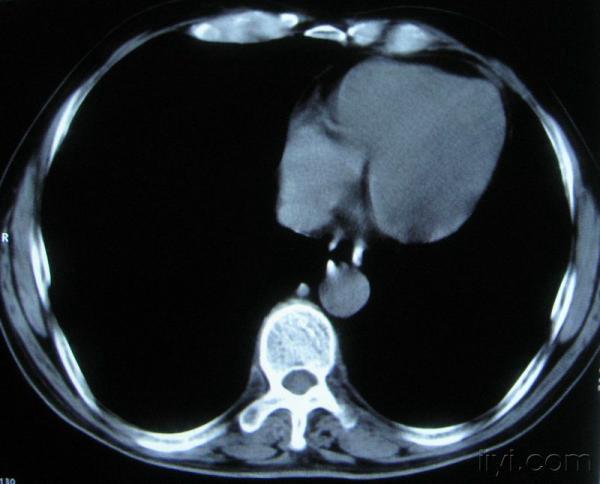

男。60岁,胸片示支气管炎治疗后复查CT。

你指那个肯定是淋巴结,中央系坏死,这很常见,特别在双侧腹股沟会经常看到。这个双侧腋窝及纵隔见多发小淋巴结征。

根据位置考虑应该是淋巴结,密度不均,是因为肿大的淋巴结中心液化坏死